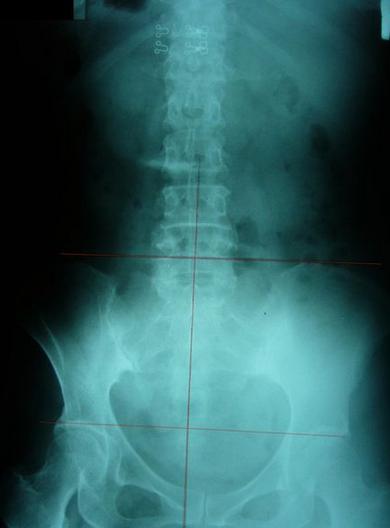

严重不对称案例,伴随腰椎向左倾斜